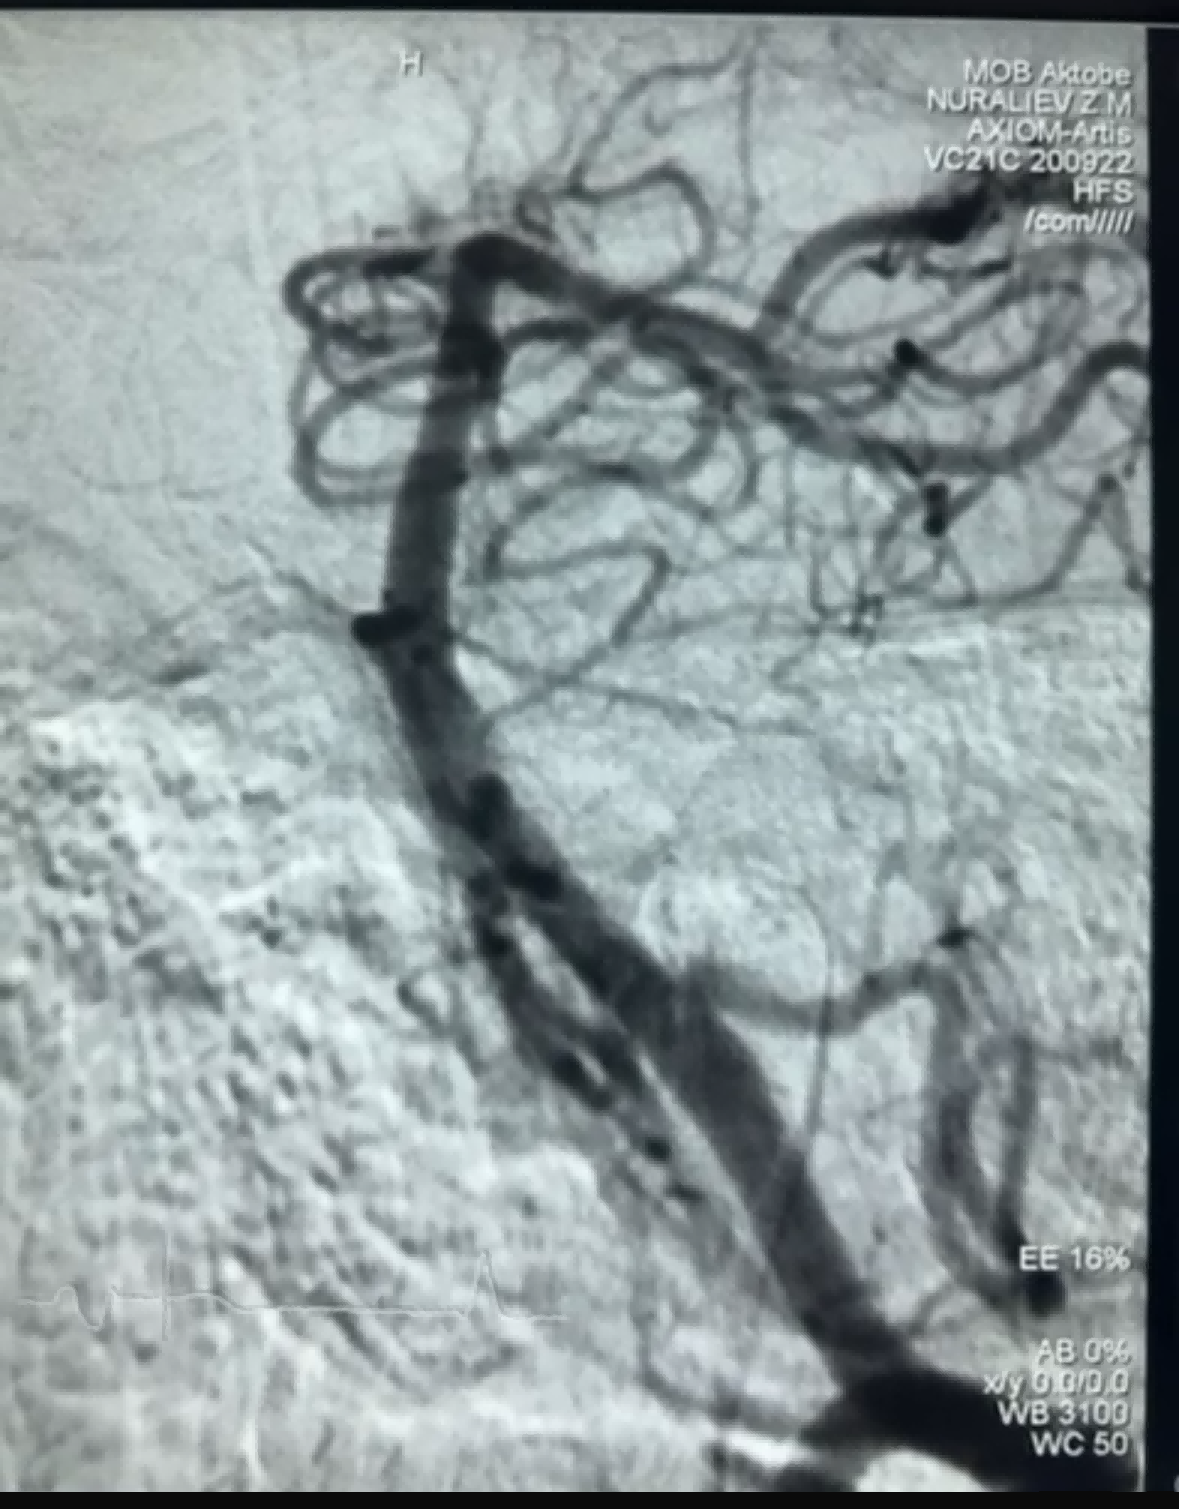

حال ہی میں، نیورو سیف میڈیکل کمپنی لمیٹڈ کے ڈریجر اسٹینٹ ریٹریور کا استعمال کرتے ہوئے ایک کامیاب تھرومبیکٹومی کیس سامنے آیا۔ ڈریجر اسٹینٹ ریٹریور میں ایک غیر حملہ آور نرم ٹپ ہے، جو اندرونی نقصان کے خطرے کو بہت حد تک کم کرتی ہے، اور اس میں ایک منفرد خصوصی شکل کا سوراخ ہے۔ ایسا ڈیزائن جو بنیادی طور پر خلا کی تبدیلیوں کو بند کرکے خون کے جمنے کو پکڑتا ہے۔